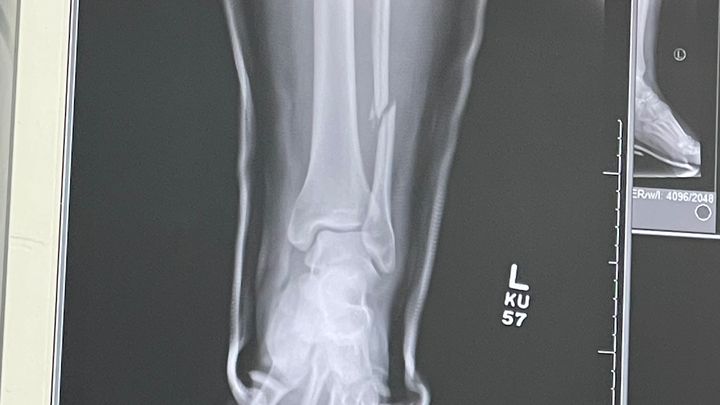

My name is Adriana. I had a terrible fall last Friday at CB Smith Park and ended up breaking my fibula and dislocating my tibia bone. At the ER, they were able to pop the tibia back into place, but I'm still left with my broken fibula. My United Health Group insurance from my job does not want to cover this surgery; they claim I have 0 surgical benefits. So, I'm left facing this huge bill for my surgery scheduled for Monday, Dec 9th. I know Christmas is around the corner, and this is my only Christmas wish. God bless you all, and thank you for reading this!